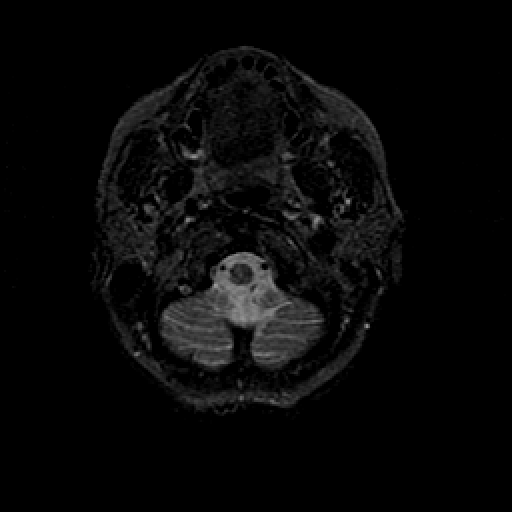

T2-weighted structural MR: Slice 5

Slice 5